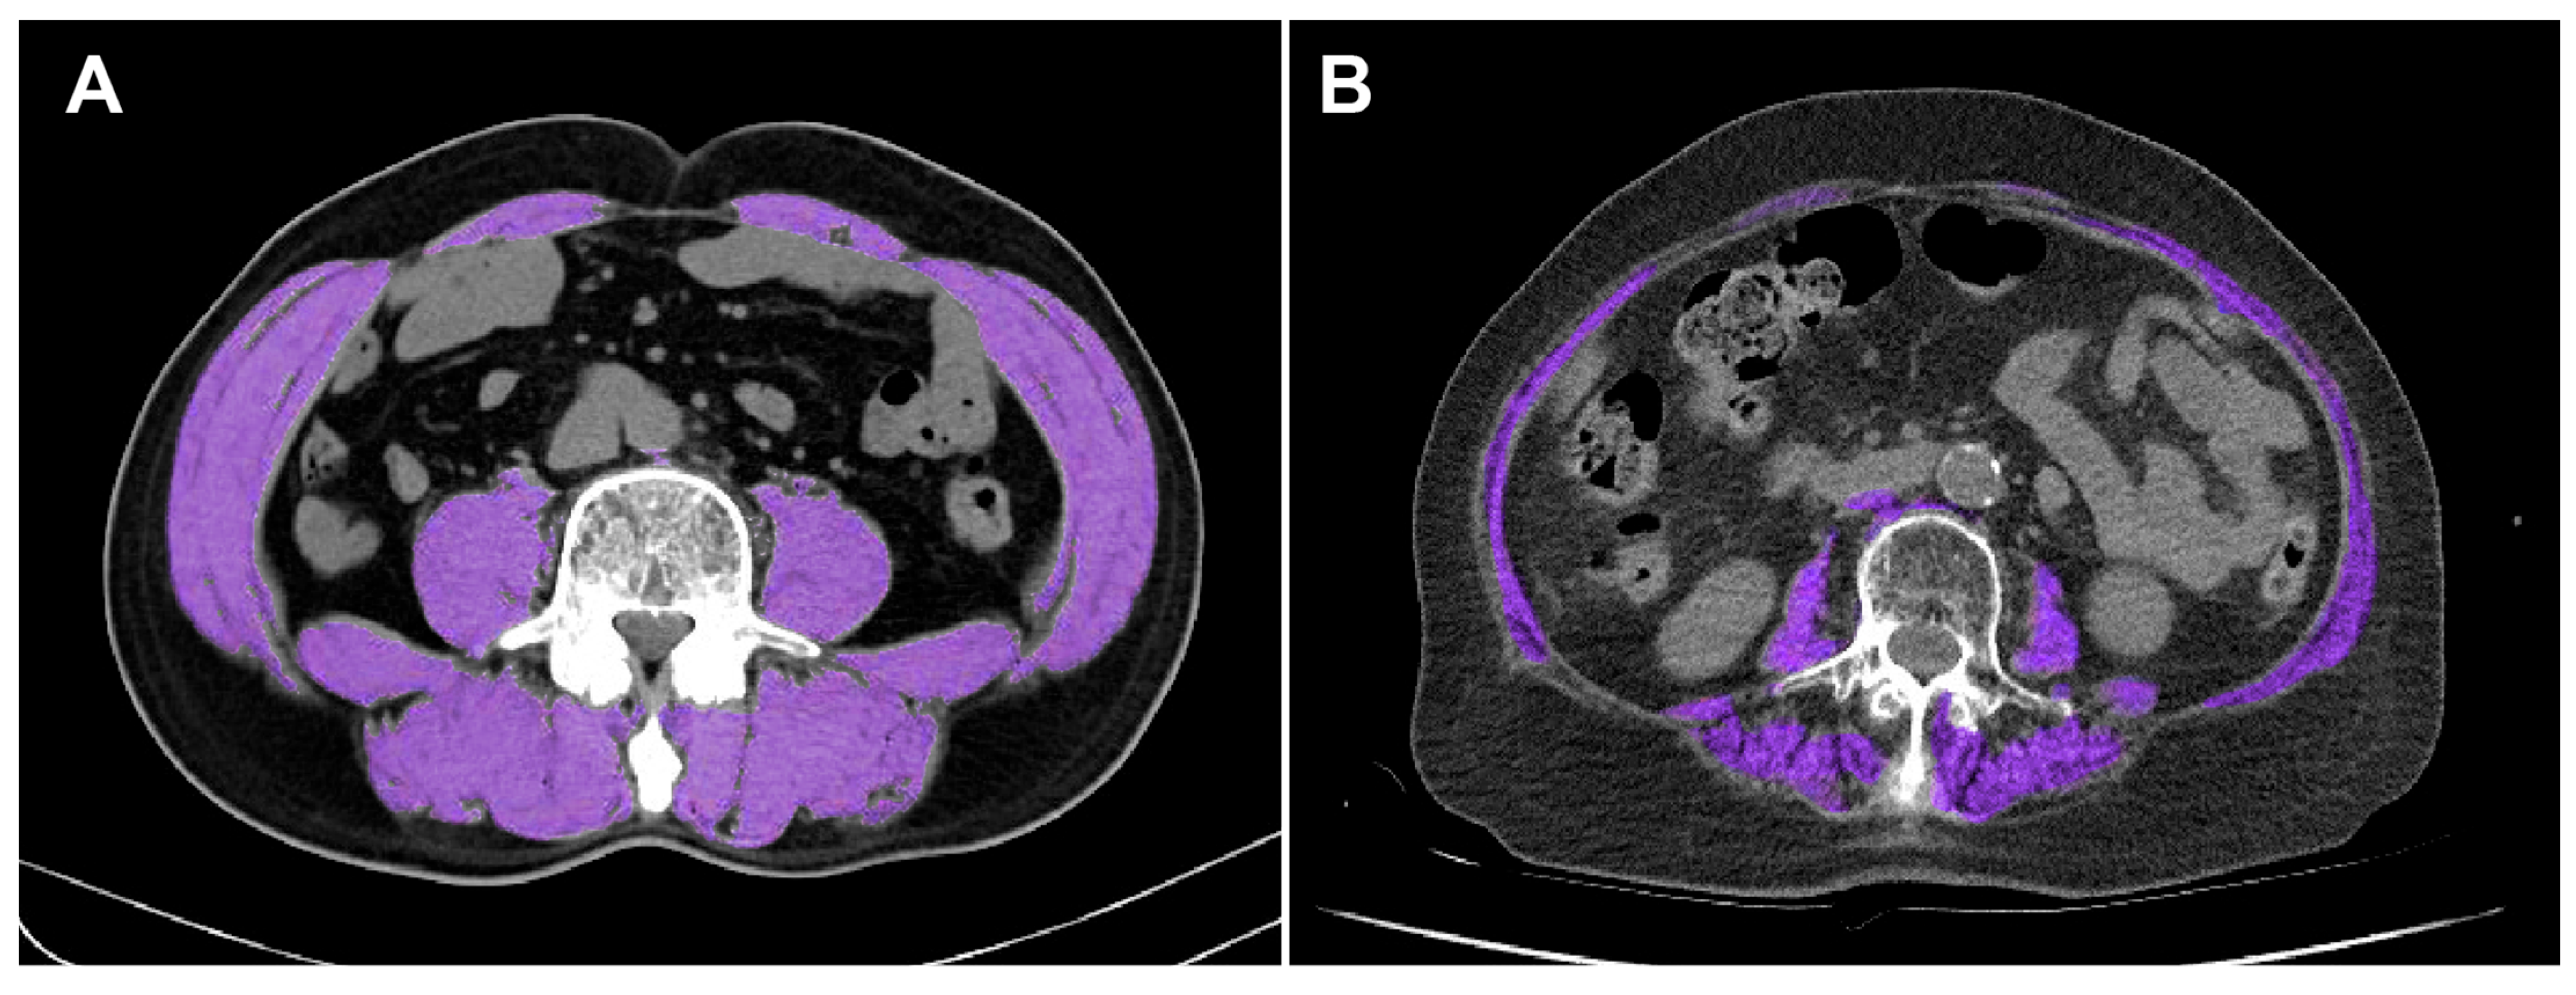

2.3. SMI Calculation

- Asan J-Morphometry. Available online: https://datasharing.aim-aicro.com/morphometry (accessed on 15 July 2025).

- Schneider, C.A.; Rasband, W.S.; Eliceiri, K.W. NIH Image to ImageJ: 25 years of image analysis. Nat. Methods 2012, 9, 671–675. [Google Scholar] [CrossRef]